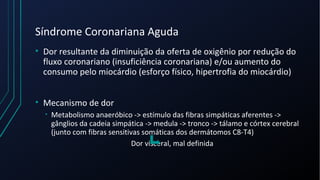

Dor torácica pode ter diversas causas, incluindo cardíacas como síndrome coronariana aguda, dissecção de aorta e pericardite, e não cardíacas como problemas pulmonares, musculoesqueléticos e do trato gastrointestinal. É importante avaliar a história clínica, características da dor e exame físico para identificar a possível causa e orientar o tratamento adequado.